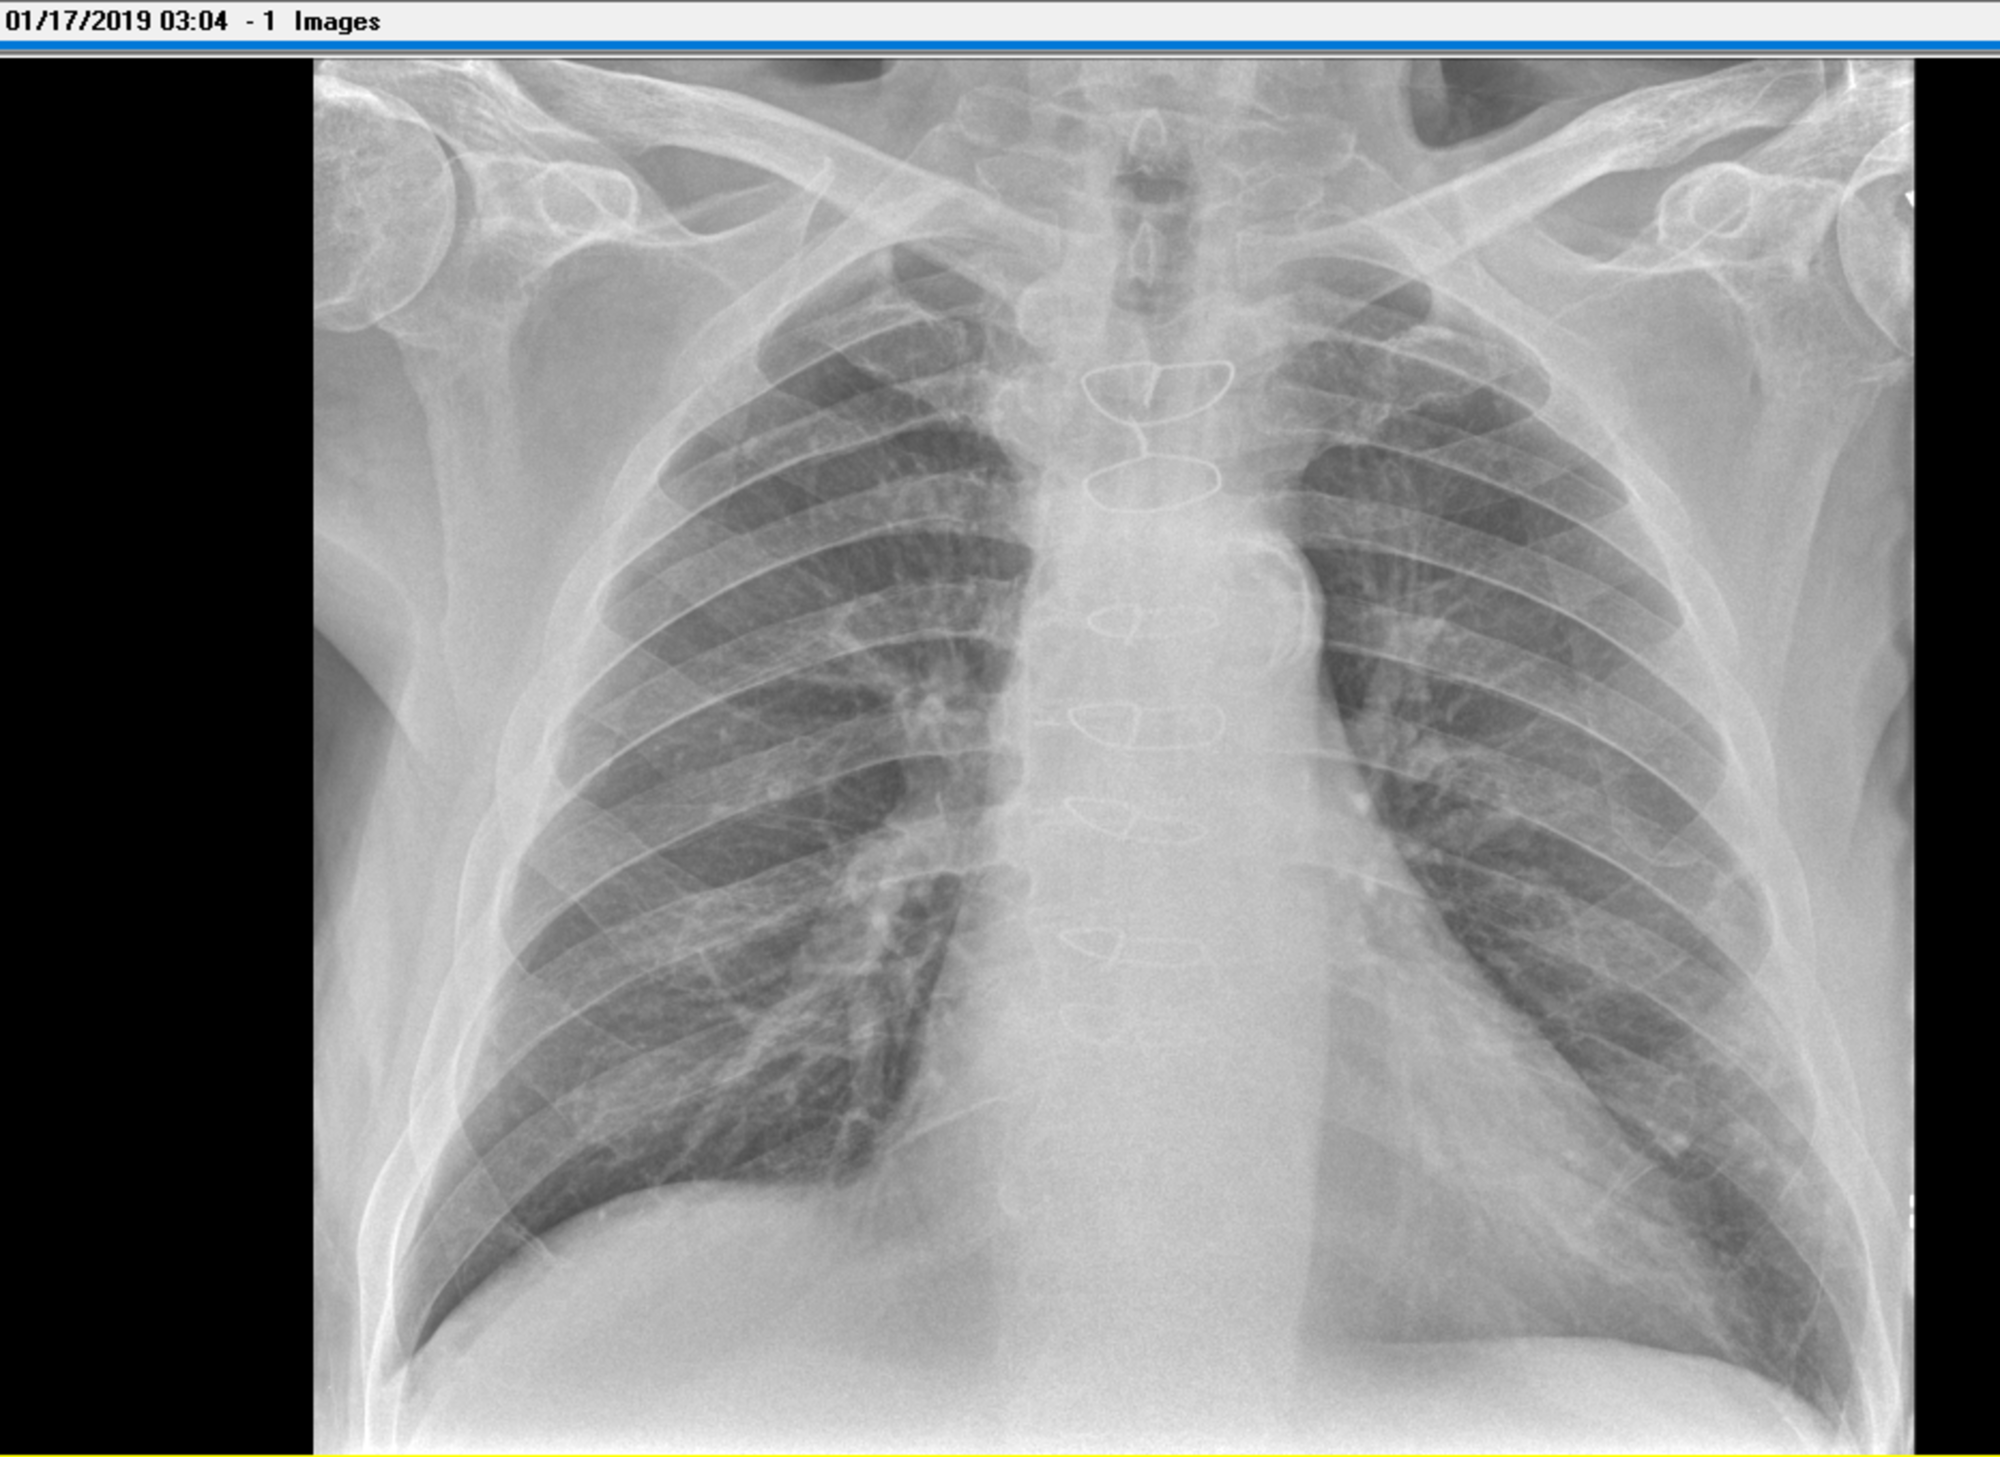

View What Is Chest X Ray Report US. Data contains two files, one for images and the other. In fact every radiologst should be an expert in chest film reading.

Chest radiographs are the most common film taken in medicine. Pneumonia, atelectasis, pneumothorax, pleural effusion. What does the equipment look like?

What we see is actually the highest point of the right diaphragm, which is anterior to the pneumonia in the right lower lobe.

Data contains two files, one for images and the other. What does the equipment look like? Data contains two files, one for images and the other. Pneumonia, atelectasis, pneumothorax, pleural effusion.